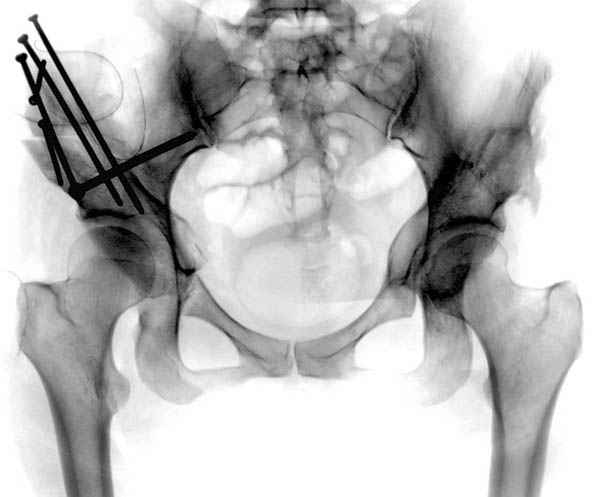

В развитых ортопедических центрах после дисплазии в молодом возрасте для сохранения сустава периацетабулярная остеотомия стала стандартом лечения.

Как я отметил, даже "для больного 40 лет (с оптимистическим расчетом на ревизионное эндопротезирование через 15 лет) это важно" мы бы рекомендовали коррегирующию периацетабулярную остеотомию с ревизией сустава и остеопластикой импинжмента шейки.

Цель периацетабулярной операции - восстановление нормальных взаимоотношении в суставе, поэтому рекомендуемые остеотомии в молодом возрасте предназначены для профилактики дальнейшего разрушения сустава.

Кстати, после остеотомии и удаления нагрузки от проекции кист в нашей серии были самостоятельное выздоровление кисты и зарастание фрагментированного участка стенки кисты даже после минимальной фиксации.